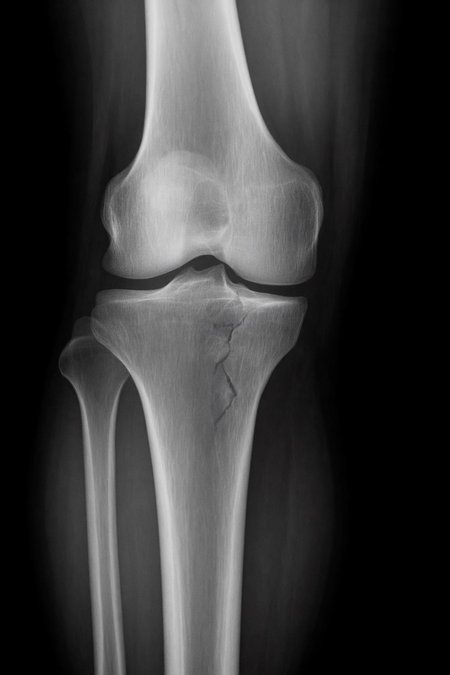

Can a model like Flux Kontext, designed for editing art and photography, be used to work with medical images, for example, with something 'as simple' as red-marking fractures?

The quick answer: it does do something interesting, but it over-scores and is far from reliable as a medical tool. It's a prototype to play with the idea, nothing more.

Even more aggressive settings (e.g. rk beta57 to denoise 1.0) reach the absurd: 100% false positives and 100% detection: it paints everything red and almost hits all fractures beyond marking healthy areas, for an untrained eye.

Not good for:

Diagnose nothing serious.

Replacing a doctor, not even close!

Important

This LoRa is for visual experimentation only. It is not a medical device, it is not reliable and should not be used for clinical diagnosis.

Of course, taking into account that it is open source, fast (25 seconds per analysis) and that it can run on desktop computers, I think it is worth continuing to experiment with this concept in the future... we will see!